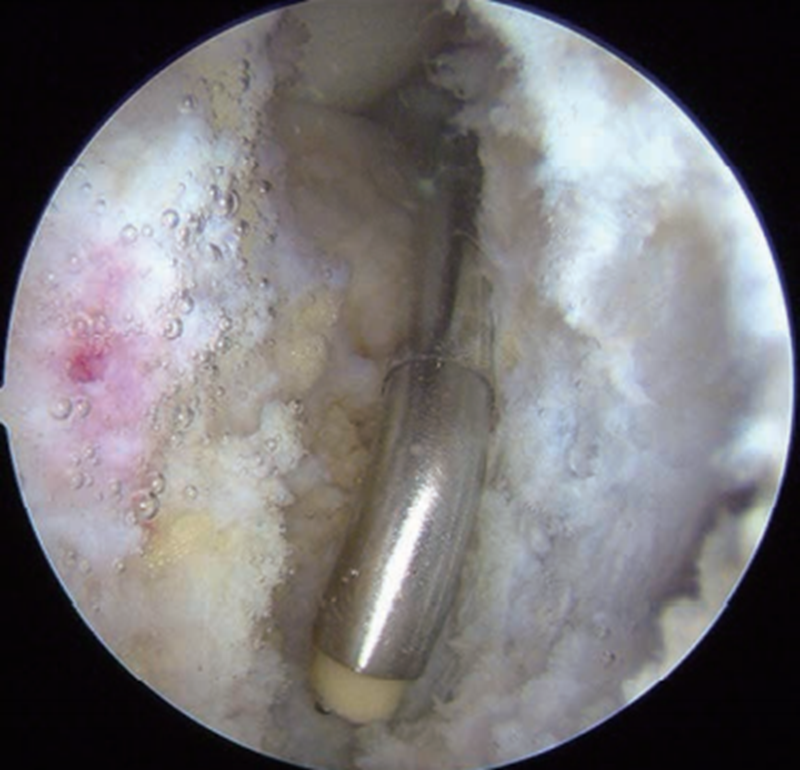

胫骨隧道外口放置在胫骨嵴偏外侧(图10),能更好地减少PCL移植物转折角以及在胫骨隧道内口的接触应力,降低韧带磨损或过度负荷。以后内侧入路为观察通道,从后外侧入路插入关节镜通道鞘管以保护后方血管、神经。直视下打入导针后,用移植物同号直径空心钻制备胫骨隧道。预置牵引线,并将关节镜通道鞘管置入牵引线前方以备协助牵拉移植物经过隧道。牵引线穿过胫骨和股骨隧道,在后方关节镜鞘的辅助牵引下将移植物引至合适位置。先固定股骨侧,固定胫骨侧前应将膝关节置于0°~30°屈伸范围,向前托起胫骨,避免其后坠,用9.1kg(20lb)的力量拉紧移植物并将其固定于胫骨侧(图11)。

图11 重建后的PCL

股骨止点周围组织是保留的原PCL残端